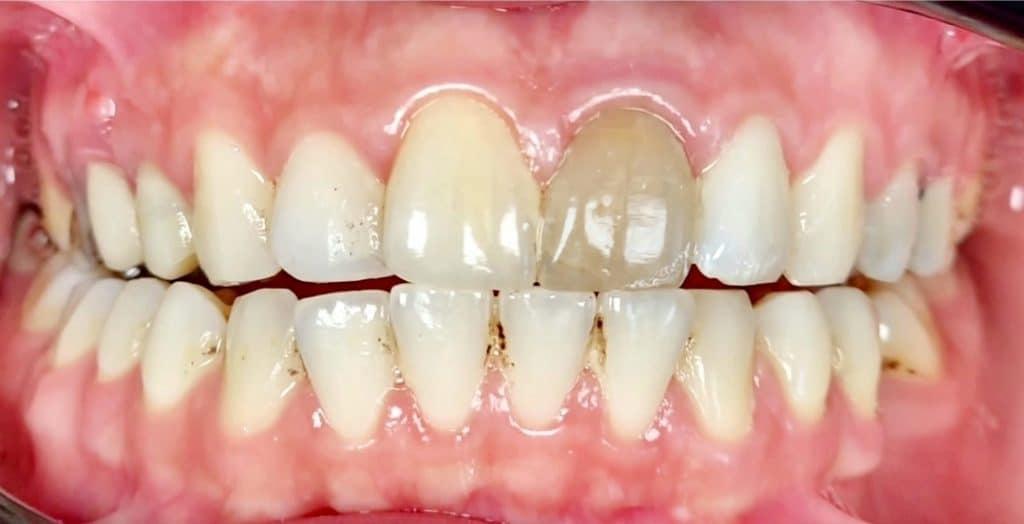

Endo treated left central incisor 11 years ago for 30 yrs old female.